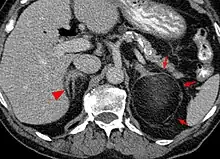

| An adrenal myelolipoma | |

Myelolipoma (myelo-, from the Ancient Greek μυελός 'marrow'; lipo, 'of, or pertaining to, fat'; -oma 'tumor or mass'; also myolipoma) is a benign tumor-like lesion composed of mature adipose (fat) tissue and haematopoietic (blood-forming) elements in various proportions.[1]

Myelolipomas can present in the adrenal gland,[2] or outside of the gland.[3]